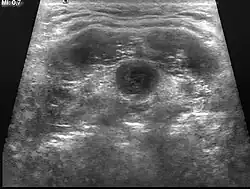

Eine angeborene Halsfistel hatte zuerst Johann Nepomuk Hunczovsky 1789 beschrieben, im Jahr 1829 auch Karl Heinrich Dzondi. Hunczovsky heilte diese durch Injektion von Weingeist bzw. Spaltung des Fistelganges.[1] Die mediane Halszyste wird meist als prallelastische Schwellung in der Halsmitte getastet. Beim Schlucken zeigt sie eine Auf- und Abbewegung. 75 % der Zysten werden vor dem 6. Lebensjahr diagnostiziert. Im Ultraschall kann ein flüssigkeitsgefüllter Hohlraum gesehen werden. Eine mediane Halsfistel stellt eine kleine Hautöffnung etwa in Halsmitte dar, aus der trübes, auch eitriges Sekret austreten kann.